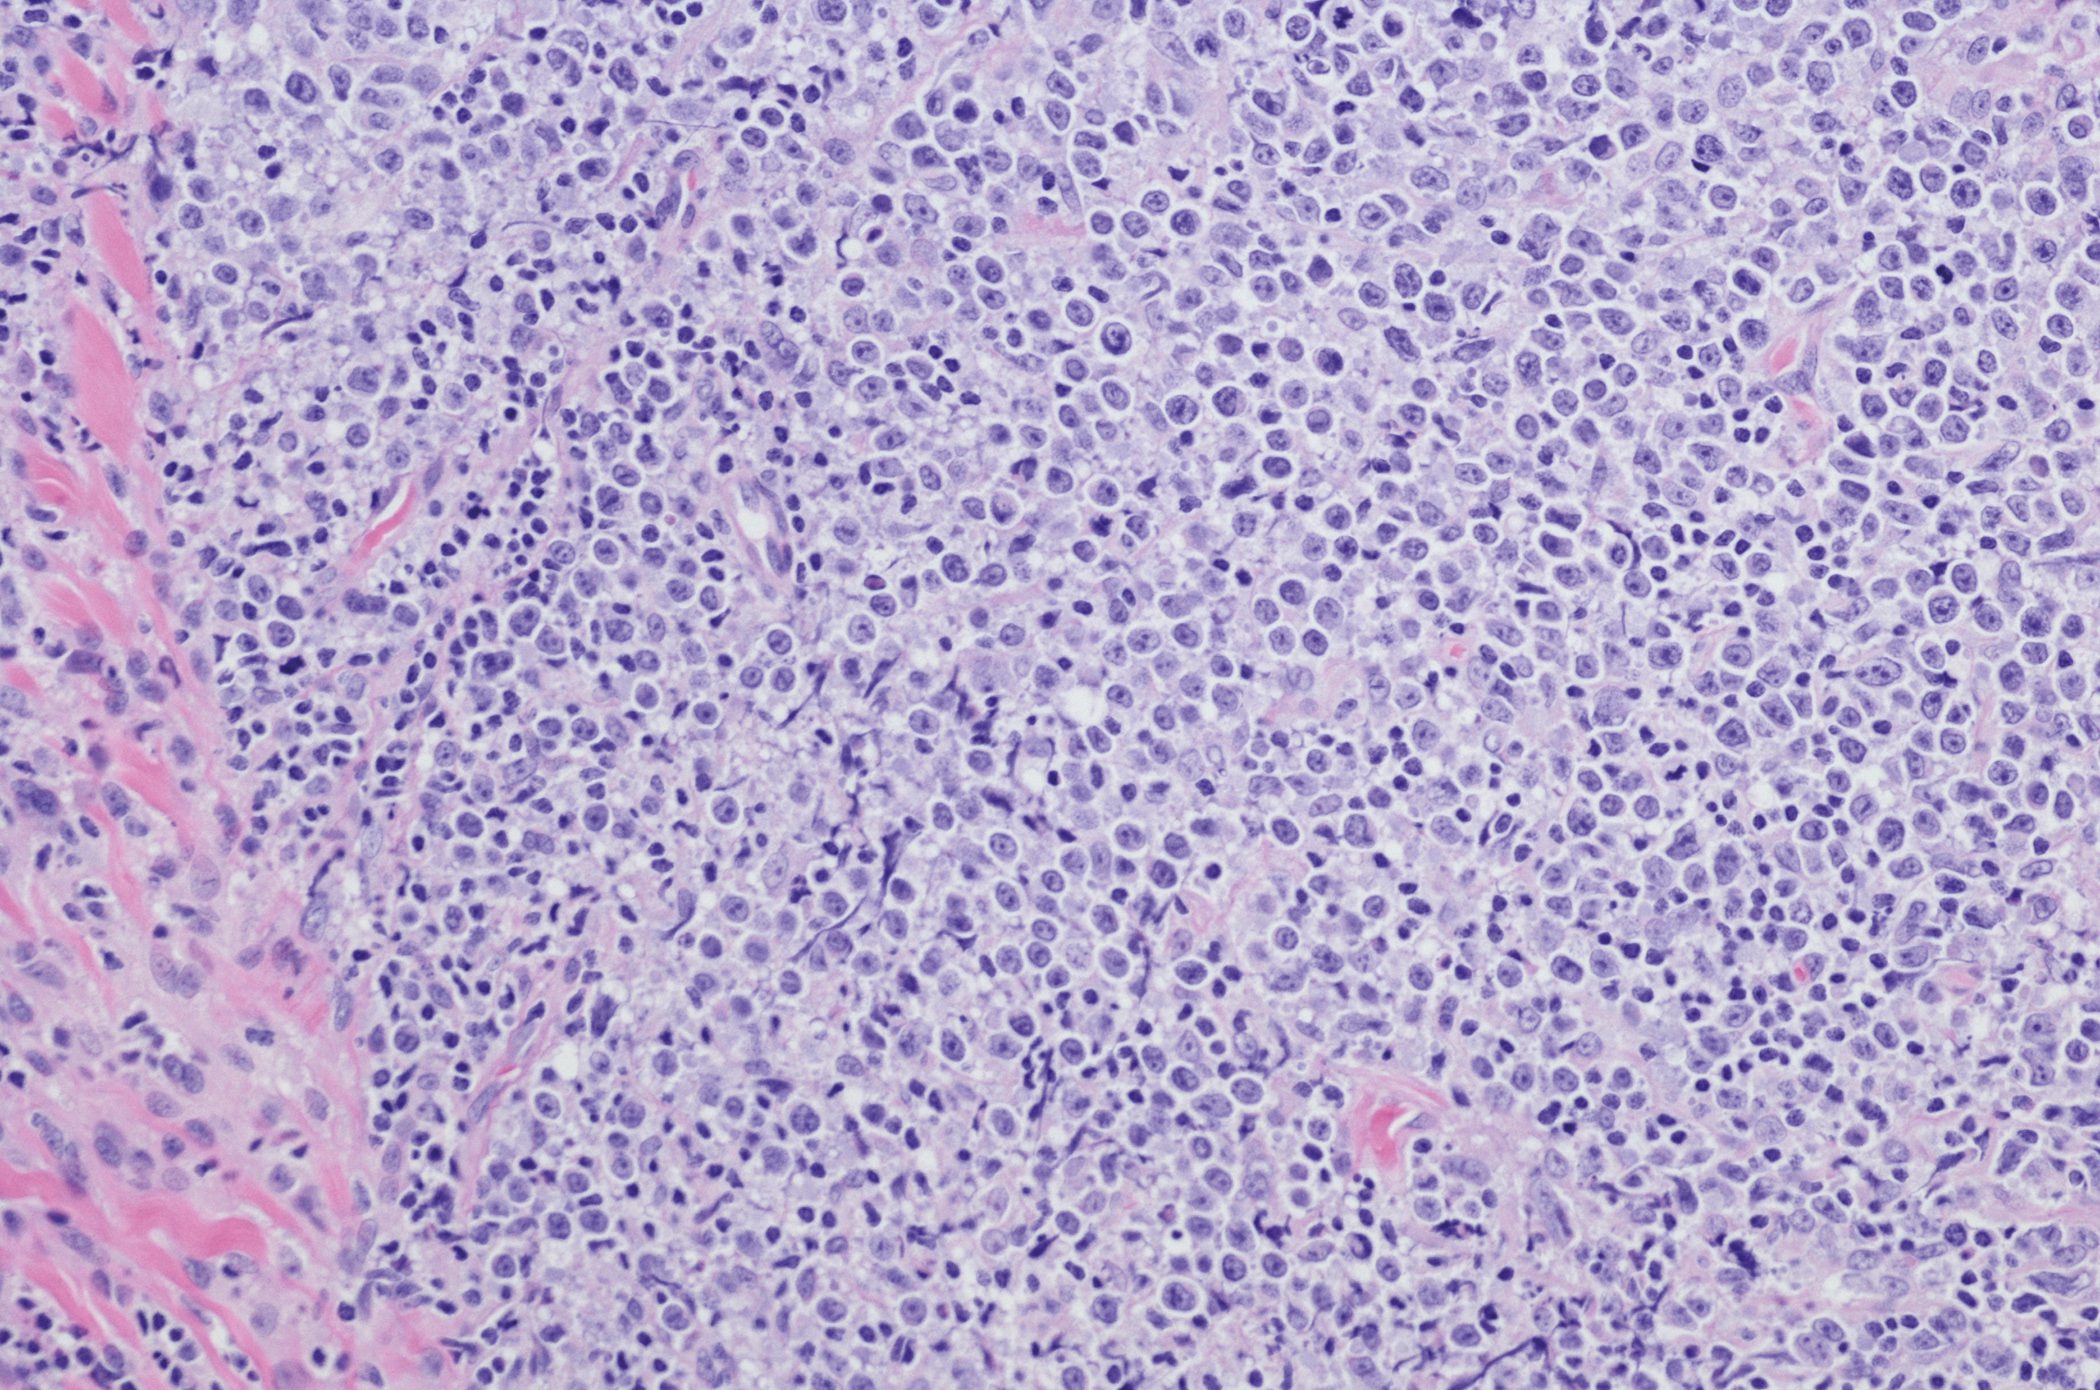

Patienten mit einem Weichteilsarkom klagen häufig über lokal umschriebene Druckgefühle und zunehmende Schmerzen. Neben der Sonografie sind insbesondere kontrastmittelgestützte CT- und MRT-Bildgebung aufschlussreich. Besteht aufgrund der Bildgebungsbefunde ein Verdacht auf einen malignen Weichteiltumor, ist eine histologische Abklärung mittels Biopsie indiziert. Heutzutage reicht hierzu häufig eine Feinnadelbiopsie aus.